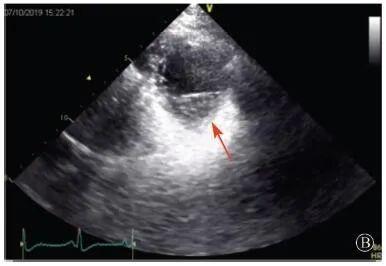

案例介紹:患者男性,20歲,因?yàn)?quot;胸痛4個(gè)月,加重1月余"于2019年7月10日入院?;颊?019年4月無(wú)明顯誘因出現(xiàn)心前區(qū)隱痛,VAS 3分,無(wú)放射,無(wú)胸悶、憋氣、活動(dòng)后氣短,每月發(fā)作1~2次,未在意。同年5月體檢發(fā)現(xiàn),肌酸激酶(CK)2928 U/L、肌酸激酶MB質(zhì)量(CK-MB)46 U/L、心肌肌鈣蛋白I(cTnI)0.055 ng/ml。6月初,患者"感冒"后出現(xiàn)心前區(qū)疼痛加重,為過(guò)電樣疼痛,VAS 5分,無(wú)放射,持續(xù)約30~60 min可好轉(zhuǎn),胸痛每周約發(fā)作2次,否認(rèn)呼吸困難、胸悶、心悸,否認(rèn)活動(dòng)耐量下降。6月8日,患者就診于外院查血生化:CK 1 215→1433 U/L,CK-MB 47 U/L,cTnI 30.17→31.79 ng/L;血脂(-);抗核抗體譜(-);超聲心動(dòng)圖:左室增大,左室舒張末內(nèi)徑57 mm,左室射血分?jǐn)?shù)39%,輕度二尖瓣關(guān)閉不全;磁共振心肌灌注延遲動(dòng)態(tài)成像(圖1):左室稍增大,收縮功能稍減低;基底部至心尖部左室下壁及側(cè)壁、心尖部左室前壁心外膜下心肌纖維化,考慮非缺血性心肌病;肌電圖:肌源性損害(偏慢性)。診斷"多發(fā)性肌炎、心肌損傷",予患者倍他樂(lè)克緩釋片23.75 mg/d、培哚普利0.5 mg/d、螺內(nèi)酯20 mg/d口服,患者未再出現(xiàn)心前區(qū)疼痛,但步行1 km左右會(huì)出現(xiàn)氣短、乏力。為進(jìn)一步明確心力衰竭病因收入我院。患者上高中起出現(xiàn)體育課等劇烈活動(dòng)后雙下肢明顯乏力,不能耐受1 km長(zhǎng)跑類運(yùn)動(dòng),日常體力活動(dòng)不受影響,否認(rèn)肌肉酸痛等不適。此次發(fā)病以來(lái),一般情況尚可,否認(rèn)尿量減少,體重?zé)o明顯變化。既往史:否認(rèn)高血壓、冠心病、糖尿病病史。個(gè)人史:否認(rèn)特殊毒物藥物接觸史,無(wú)煙酒嗜好?;橛?、家族史:未婚未育,否認(rèn)家族類似病史,否認(rèn)遺傳病史。入院查體:脈搏69次/min,血壓112/70 mmHg,指氧(自然狀態(tài))98%,體質(zhì)指數(shù)21.1 kg/m2;無(wú)皮疹;雙肺呼吸音清;心律齊,未聞及雜音;肝脾不大;雙側(cè)腓腸肌肥大,肌肉無(wú)壓痛;四肢肌力Ⅴ級(jí)、肌張力正常。雙下肢不腫。輔助檢查:入室床旁超聲心動(dòng)圖提示左室壁運(yùn)動(dòng)普遍減低,心尖部、左室下后壁為著,肌小梁增多。

左室壁較廣泛心外膜下延遲強(qiáng)化,可見(jiàn)左室下后壁肌小梁增多(箭頭所示)

圖1 患者外院磁共振心肌灌注延遲動(dòng)態(tài)成像